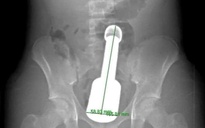

Hình ảnh chiếc chày kim loại dài 18 cm mắc kẹt trong hậu môn thiếu niên 15 tuổi

ẢNH: BỆNH VIỆN ĐA KHOA HÀ ĐÔNG